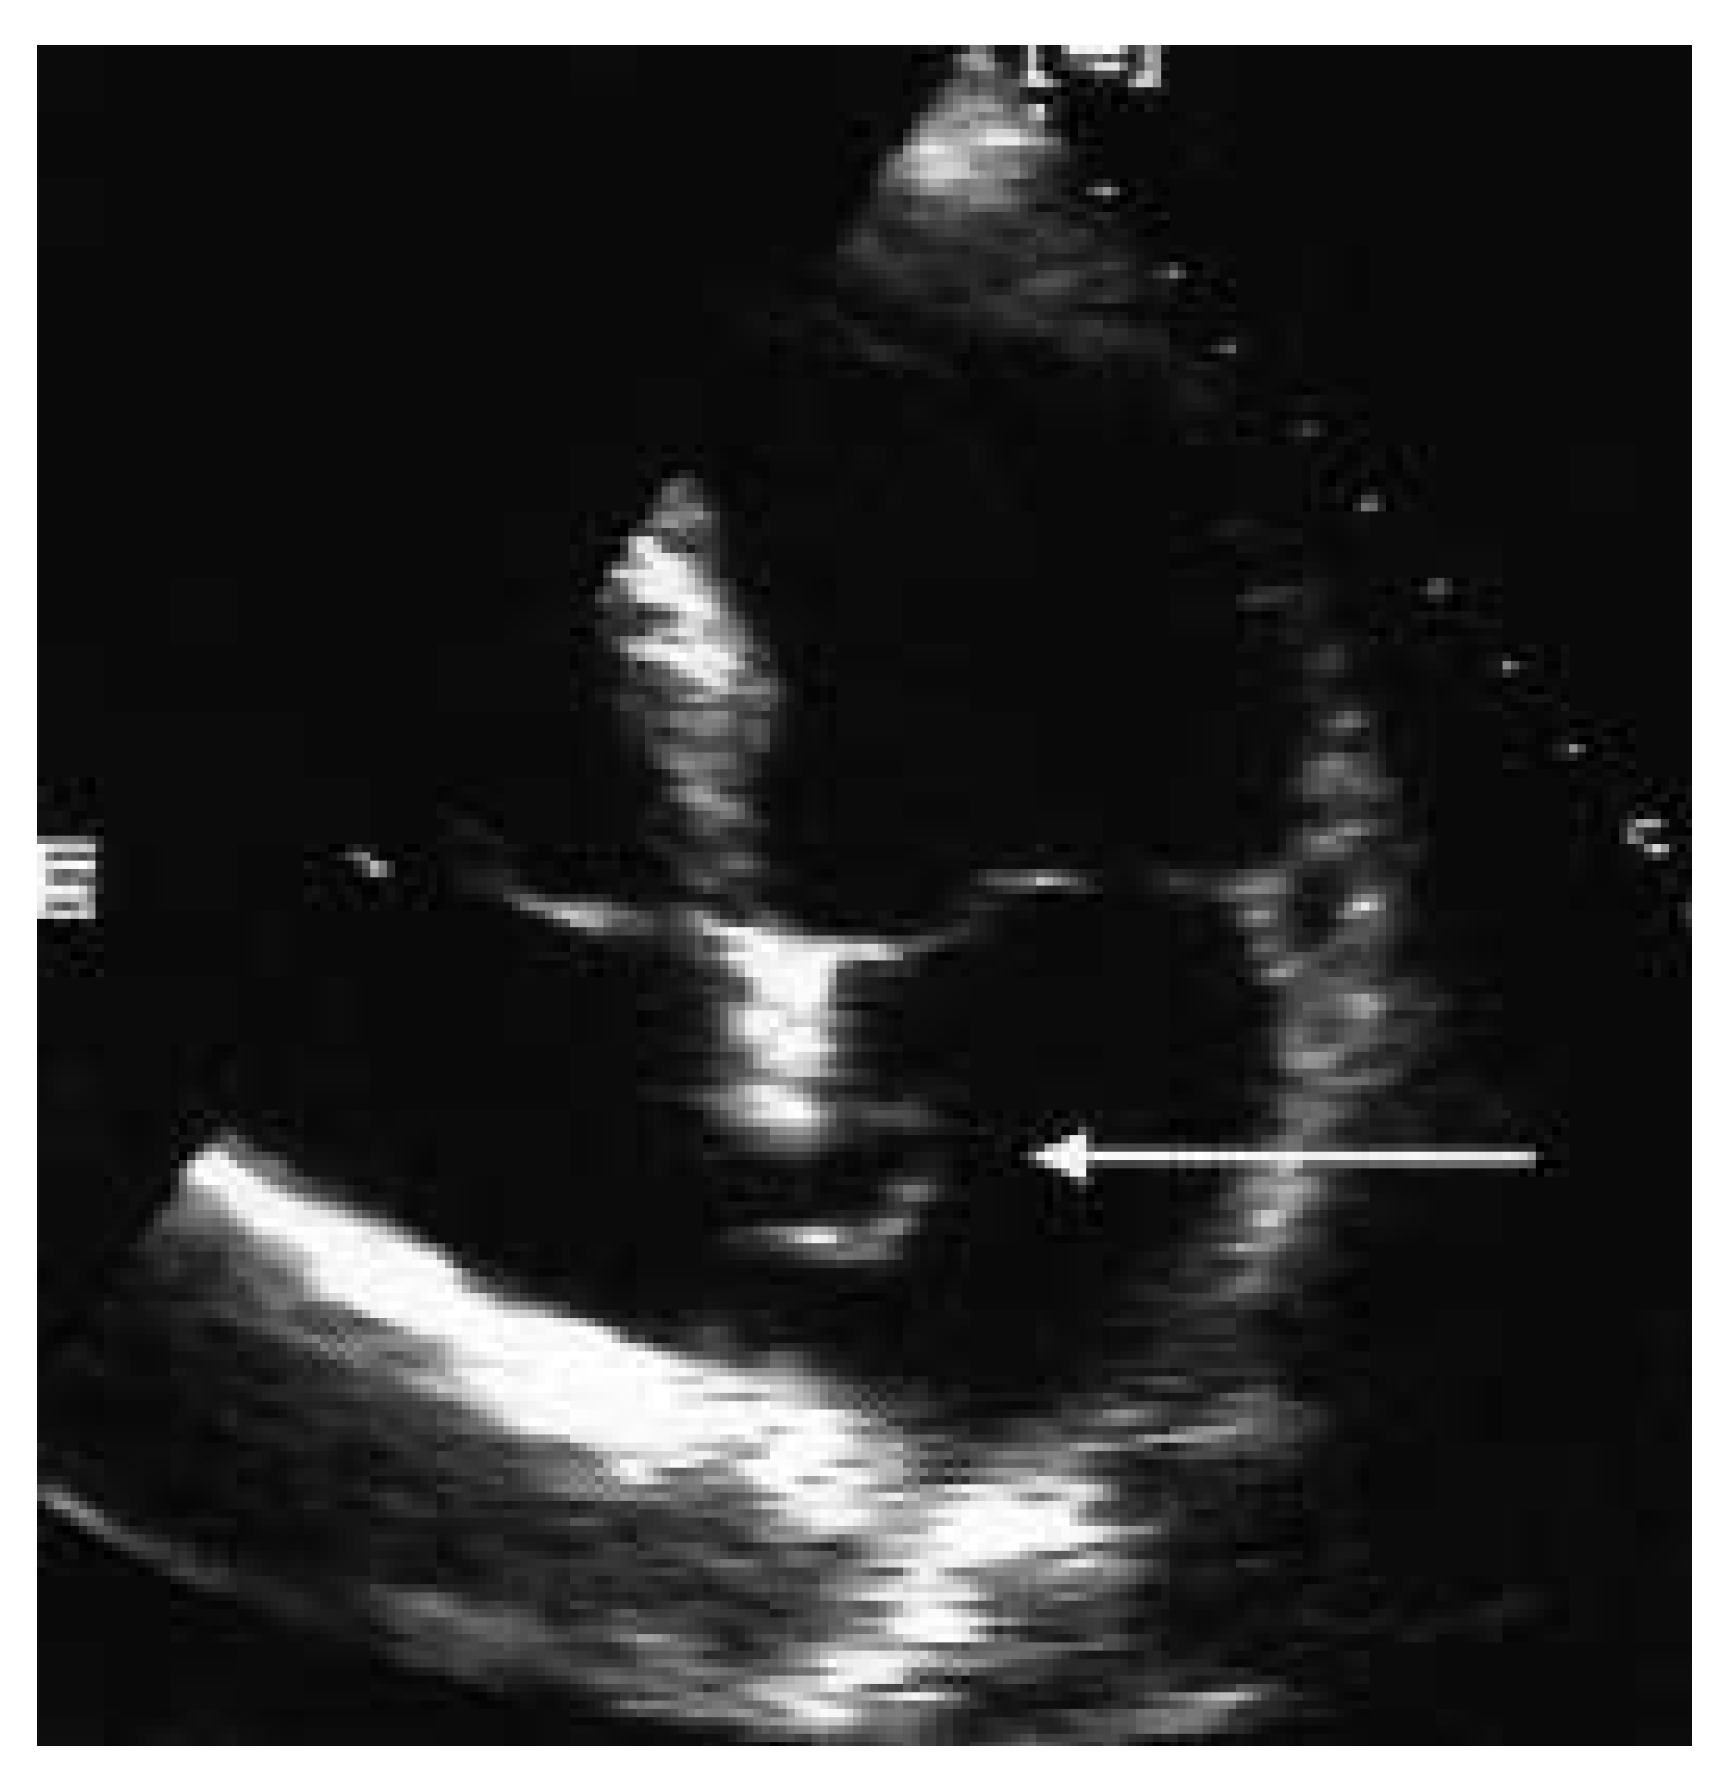

In der transthorakalen Echokardiographie fand sich eine linksventrikuläre Hypertrophie bei normaler systolischer Funktion. Zusätzlich bestand eine minime Mitralinsuffizienz und Aorteninsuffizienz. Es fand sich ein Vorhofseptumaneurysma mit einem kleinen Shunt auf Vorhofebene (Figure 1). Der pulmonal-arterielle Druck war entsprechend dem Doppler-echokardiographisch erhobenen Druckgradienten zwischen rechtem Ventrikel und rechtem Vorhof (30 mm Hg) nicht erhöht. In der anschliessenden transösophagealen Echokardiographie (Figure 2) konnte ein ASD Typ II im Bereich des Foramen ovale mit einem bidirektionalen Shunt, einem Vorhofseptumaneurysma und einer persistierenden Eustach-Klappe dargestellt werden.

Figure 1.

Echokardiographie mit Vorhofseptumaneurysma.